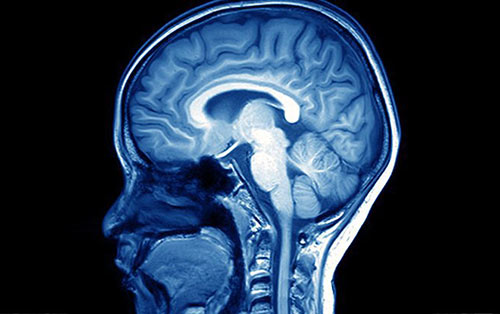

Có nhiều loại gen liên quan đến trí thông minh (Ảnh: Shutterstock)